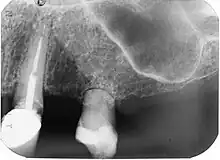

| Diagnostic method | Dental examination, X-rays |

It may also present as an incidental, radiographic finding. Radiographically, a radiolucent area of uniform density within the root canal may be visible with well-defined borders. Canal walls may appear sclerosed, thus the outline of pulp chambers or root canals may not be followed through the lesion. Lesions may also be oval radiolucencies that are continuous with the canal walls.